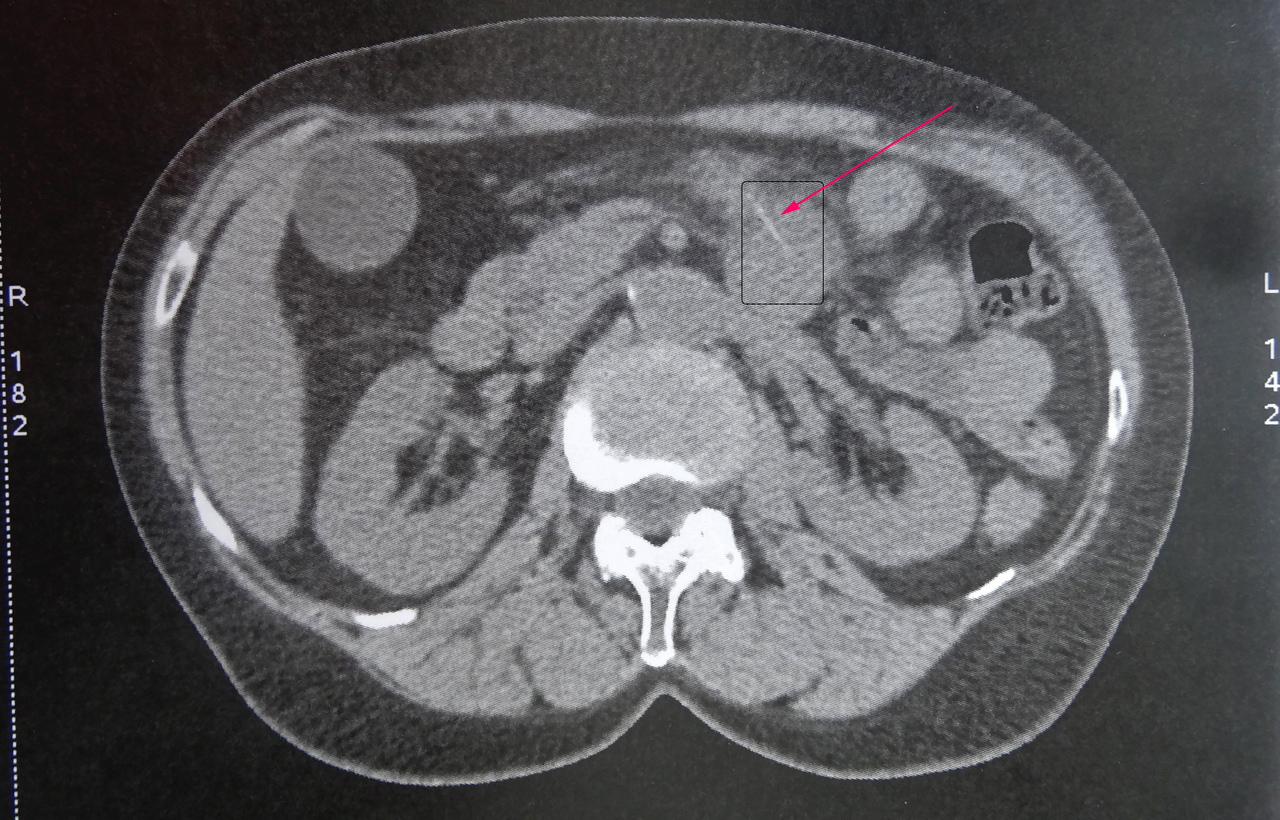

Collection P. Frances Scanner abdominal montrant une arête de poisson fichée au niveau du jéjunum (flèche rouge), à l’origine d’un début de perforation de l'intestin grêle